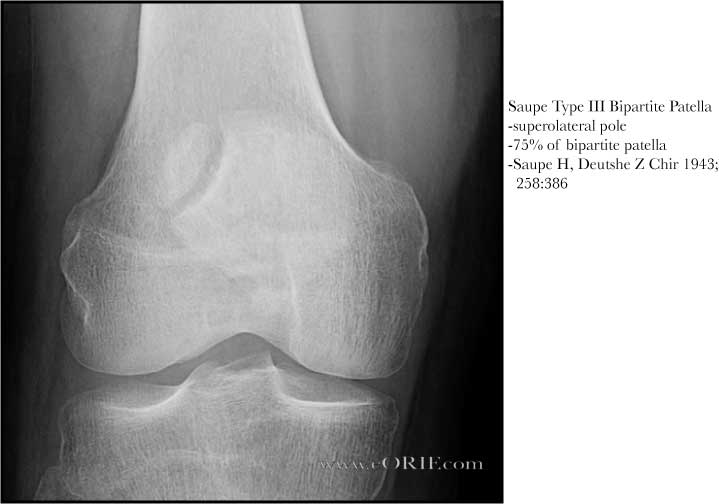

Особый вариант перелома – вертикальный, при котором линия перелома проходит сверху вниз. В подавляющем большинстве случаев такие переломы не смещаются, так как тяга мышцы направлена снизу вверх, то есть вдоль линии перелома. Однако мировой медицине известны и редкие случаи смещения таких переломов, которые могут возникнуть в том случае, когда например, мыщелки бедренной кости диспластичны и надколенник изначально был смещен в сторону (обычно кнаружи).

Осевая проекция. Вертикальный перелом. Обратите внимание на возникшую в результате смещения ступеньку на скользящей поверхности надколенника.Иногда для более точного диагноза могут потребоваться компьютерная и/или магнитно-резонансная томография, но, в подавляющем большинстве случаев, достаточно рентгенографии.

Остеохондрит коленной чашечки: его можно спутать с остеохондральным переломом коленной чашечки. Остеохондрит возникает вне травматического контекста. Необходимо быть в состоянии вызвать его перед радиологическим открытием вне травматического контекста.

Пателла Бипартита: это дефект слияния ядер оссификации, изображение находится на верхнем боковом краю коленной чашечки. Эта особенность чаще всего является двусторонней. Это изображение не зависит от травматического контекста. Двудольная надколенник обычно не болезненна.

Краевой перелом надколенника, хорошо видимый на аксиальной рентгенограмме.